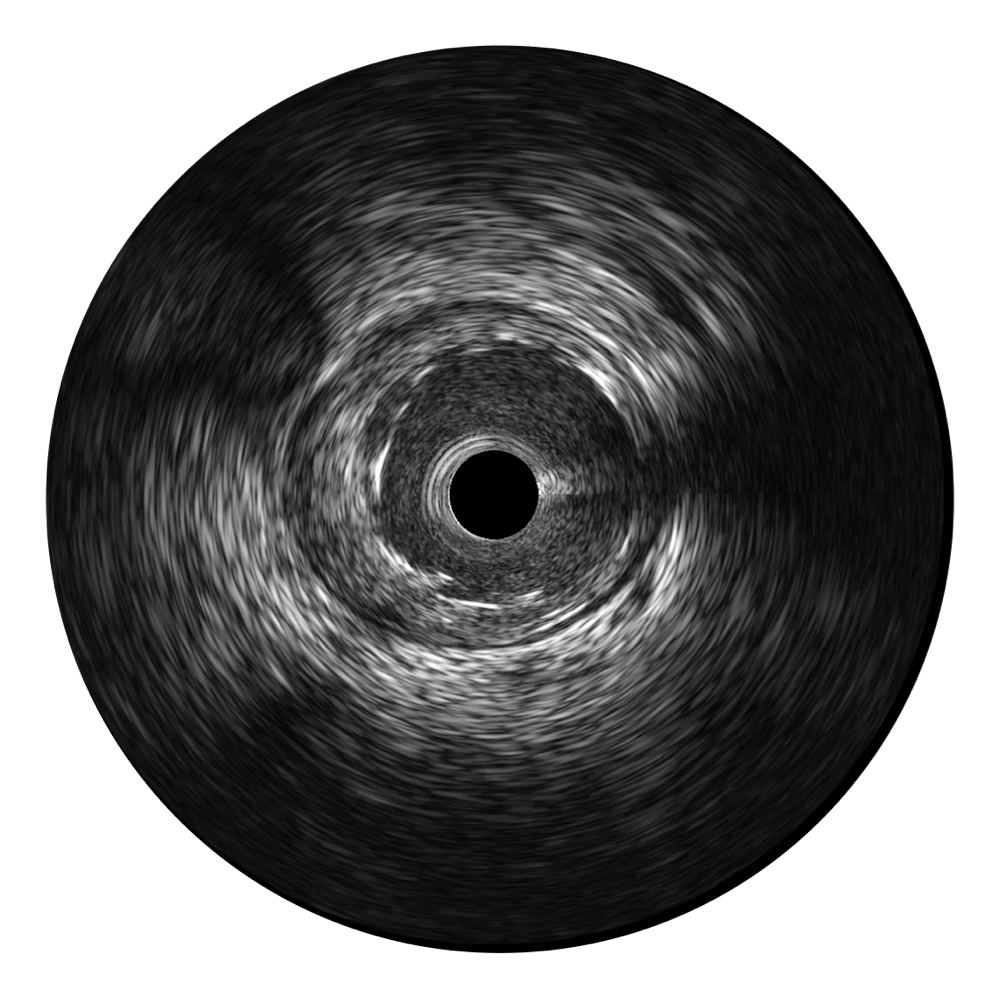

治疗前后两次测量录像对比

简化疗效评估

一键智能描迹,自动测量斑块负荷、面积狭窄率等指标,准确率高于90%